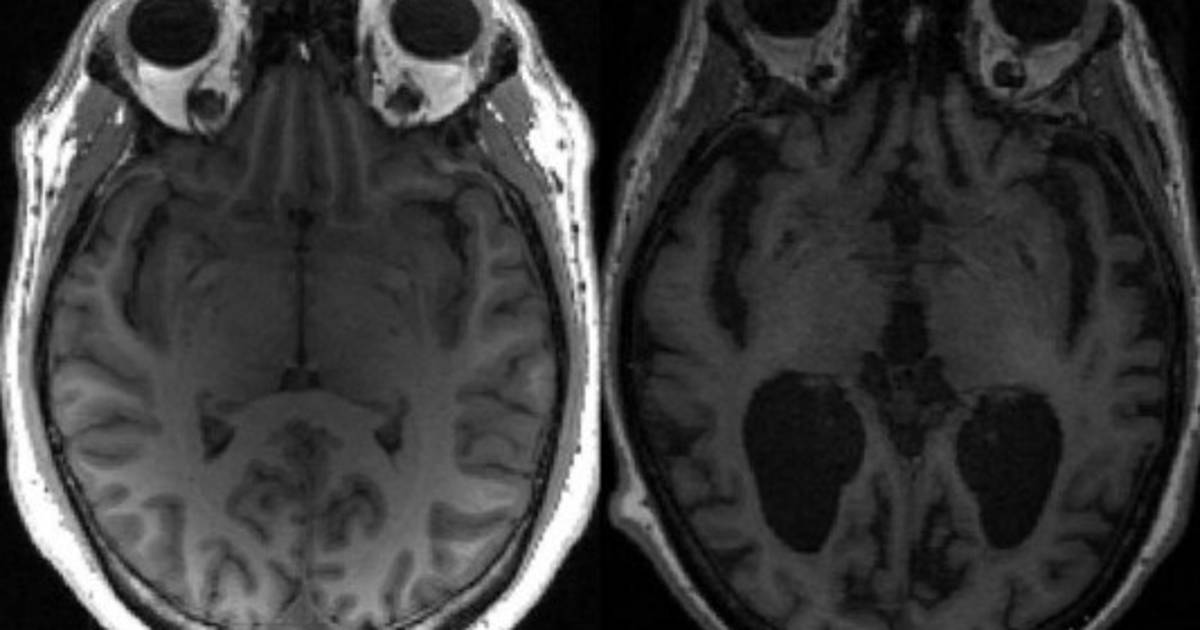

En la enfermedad de Alzheimer, tau y otra proteína llamada beta amiloide se acumulan en nudos y placas -conocidos ambos como agregados- que matan las células cerebrales y encogen el cerebro.

El grado de la enfermedad de Alzheimer se mide según la denominada 'Escala Braak'. El equipo encontró que lleva unos 35 años avanzar desde la etapa tres, cuando comienzan a aparecer síntomas leves, a la etapa seis, que es la más avanzada.

Si los agregados se duplican aproximadamente en cinco años, entonces en 35 años se habrían multiplicado por 128. Ese crecimiento exponencial 'explica porqué la enfermedad demora tanto en desarrollarse y luego la persona se deteriora rápidamente'.